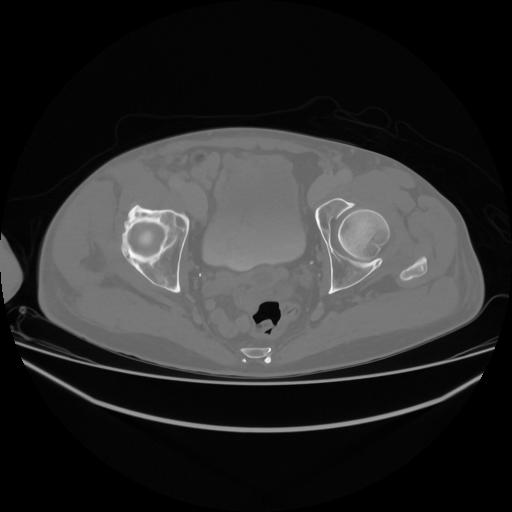

5 CUERPO,CE,Vol,1.0,CUERPO,,